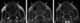

Nasolabial cyst

This nasolabial cyst, also known as a nasoalveolar cyst, is located superficially in the soft tissues of the upper lip. Unlike most of the other developmental cysts, the nasolabial cyst is an example of an extraosseous cyst, one that occurs outside of bone. [Source: Wikipedia ]